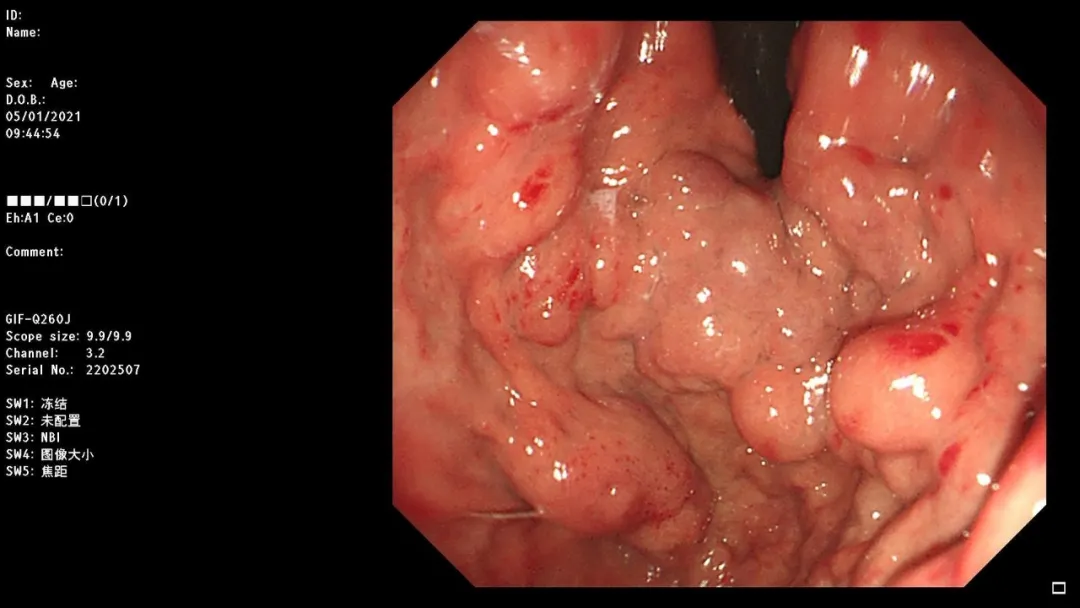

病例一:男,停止排气排便4天,CT提示乙状结肠占位,至急诊外科就诊。

South Africa red wine

急诊肠镜示:距肛门20cm新生物,占据肠腔全周,放入肠道支架通过狭窄段,粪水流出,检查诊断:乙状结肠癌并梗阻急诊肠道支架置入术。